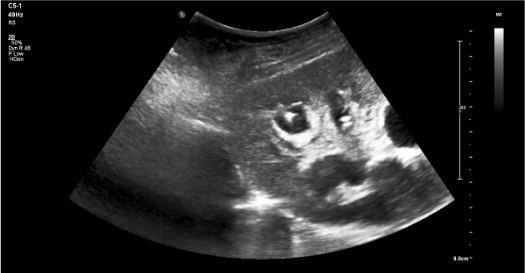

Use when the collecting system is minimally dilated and direct calyceal targeting is difficult. The first needle opacifies the system; the second needle accesses the target calyx under fluoroscopic guidance.

- 1First stick — opacification needle: Under US guidance, advance a 21G or 22G Chiba needle into the renal pelvis or any accessible calyx (precision not critical for this pass).

- 2Inject contrast: Slowly inject diluted iodinated contrast (1:1 with saline) through the first needle to opacify the collecting system under fluoroscopy. The pelvicalyceal anatomy is now visible.

- 3Identify target calyx: Under fluoroscopy, identify the posterior lower or middle pole calyx — look for the "end-on" calyx (appears as a circle, not a projection).

- 4Second stick — working needle: Under fluoroscopic guidance, advance an 18G or 21G access needle directly into the target calyx. The contrast outline makes targeting precise.

- 5Confirm access: Urine return or contrast aspiration from the working needle confirms calyceal entry. Proceed with standard wire and sheath placement.